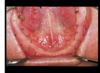

what severely compromises a denture regarding retention and stability?

if FOM is near the level of the ridge crest